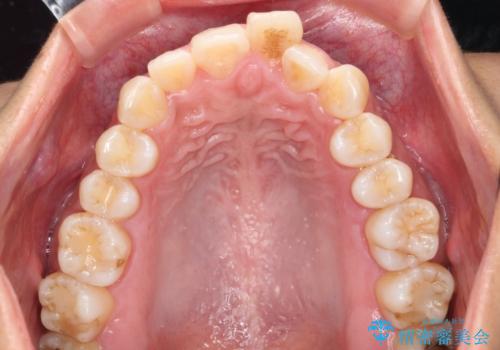

出っ歯感のある前歯を治したい、抜歯をしないマウスピース矯正

- 前歯のガタつき、突出感のある前歯の改善を求めて来院されました。

前歯の角度を改善し審美性を高めるとともに、奥歯のガタつきも並べ直すことで安定した咬合関係の確立を目指します。

歯列の側方拡大をしっかりと行ったことで歯を抜かずに前歯の角度をしっかりと改善することができました。